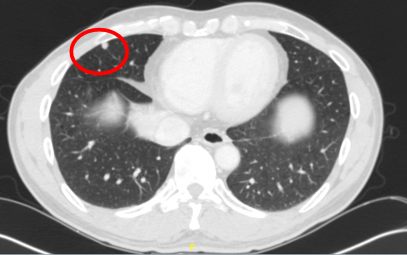

索拉非尼治疗5个月后(2014.11)本院复查,对比外院CT:右肺下叶病灶较前稍小,肝S8、S5病灶较前增大。

2014年12月第一次介入治疗:CT及超声引导下消融

60W/8min